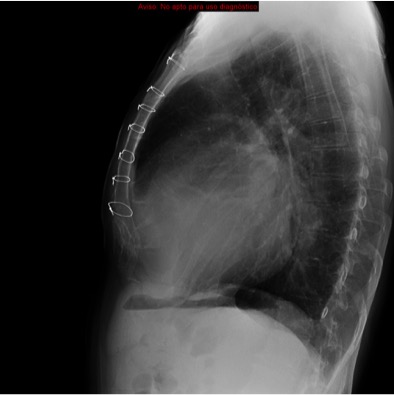

CASO: Operada de esofaguectomia y reconstrucción con coloplastia hace 3 meses. Sintomas de neumonía.

Hallazgos:

- De inicio llama la atención una densidad practicamente total del todo el hemitórax izquierdo, lo cual podría hacernos pensar que estamos ante una posible neumonía.

- Sin embargo el tórax está no está bien centrado, observar como la clavícula izquierda se encuentra casi en la mitad del pulmón, por tanto lo que vemos blanco es el mediastino ya que el tórax está rotado.

Mismo paciente, al cual esta vez se le ha tomado una radiografía en PA y en sedestación. Observar como las clavículas están equidistantes a las apófisis espinosas y como ha desaparecido el velamiento del pulmón izquierdo.

Por otra parte, paciente presenta una cardiomegalia y un discreto ensanchamiento del mediastino es probable relación con cambios postquirúrgicos.